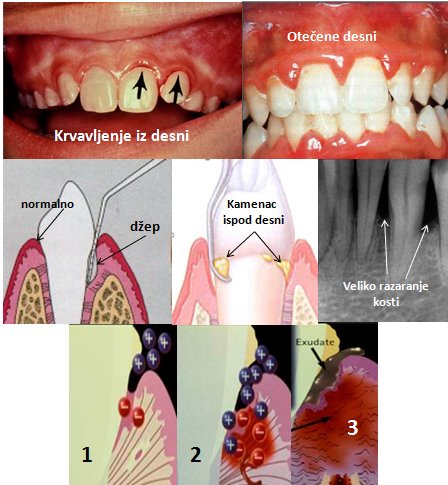

Prva i najčešća faza bolesti je upala desni (gigngivitis), koja, ukoliko se na vreme ne leči, prerasta u parodontopatiju, zahvata kost oko zuba i kasnije dovodi do pomeranja, labavljenja i napokon ispadanja zuba.

Cilj terapije parodontopatije je eliminisanje mikroorganizama iz parodontalnog džepa. Blaži oblici, kao što je upala desni, mogu se sasvim neutralisati uklanjanjem naslaga i kamenca, uz adekvatnu edukaciju pacijenata o održavanju oralne higijene.Zatim uklanjanjem supragingivalnih i subgingivanlnih naslaga oko zuba i u parodontalnom džepu.

Ako je parodontopatija uzela maha, ukoliko su prisutni parodontalni džepovi i gubitak koštanog tkiva, što se može uočiti kliničkim pregledom i analizom digitalnog radiograma, potrebno je pored kauzalne terapije ciscenja takvih dzepova i uklanjanja naslaga,primeniti i hiruske metode lecenja.